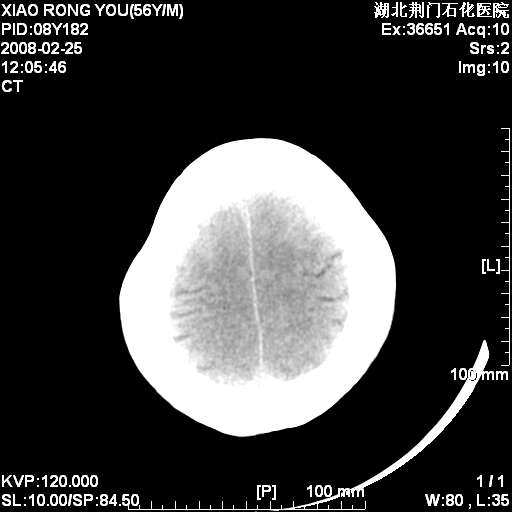

男性,68岁,多年肺结核病史。最近ct复查右肺有占位。

1月后复查

转移瘤,前后对比可发现复查片左顶叶出现一低密度灶

病变范围在一个多月时间增大,且密度不均周围有税种,并且多发!考虑转移瘤!

左枕/顶叶出现新病灶,转移瘤